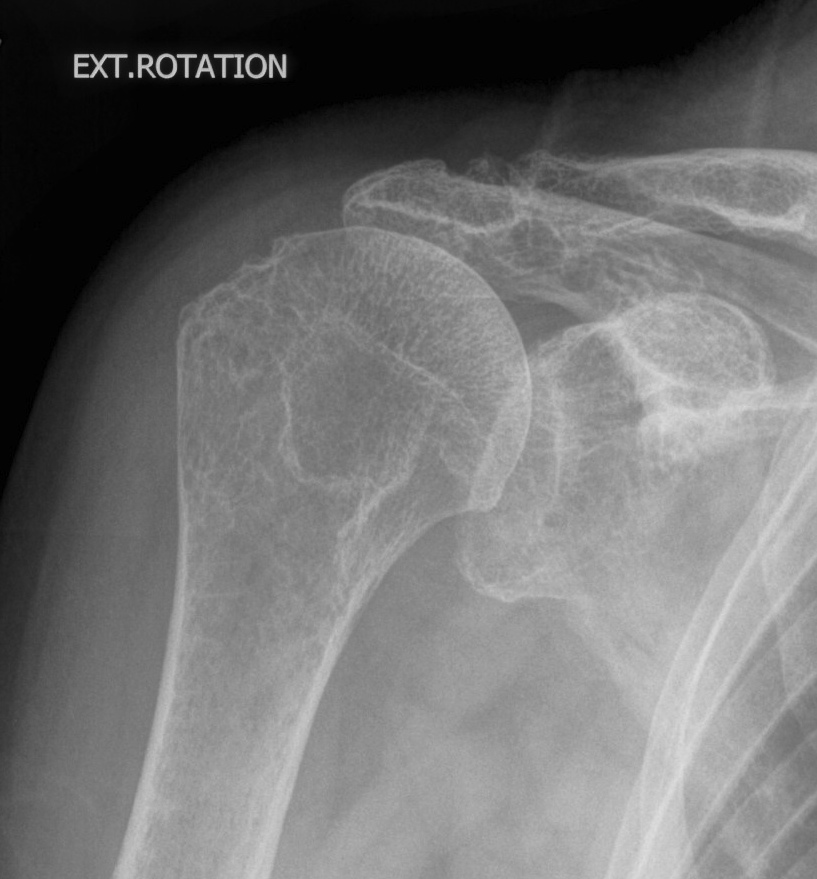

CT scan

Axial - assess glenoid bone stock / version

Coronal - look for superior wear